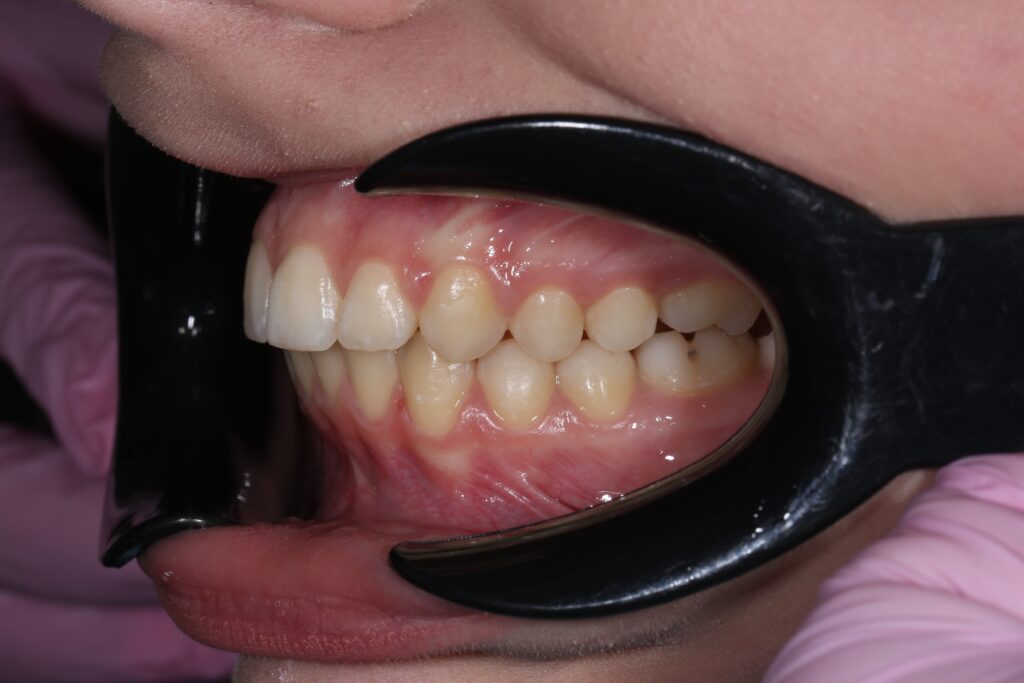

Ситуация до лечения

Диагноз: дистальный прикус, сужение, удлинение верхнего зубного ряда, скученность фронтальной группы зубов на нижней челюсти. Лечение проводилось самолигирующей брекет-системой Damon Q, срок лечения составил 2 года и 2 месяца.

Ситуация до лечения брекетами